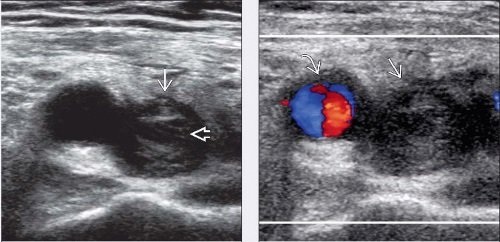

- Τρίπλεξ ( triplex ) καρωτίδων και σπονδυλικών αρτηριών κατ’ οίκον( πάχος ενδοθηλίου, έλεγχος για αθηρωτικές πλάκες, ποσοστό στένωσεις έσω καρωτίδων)